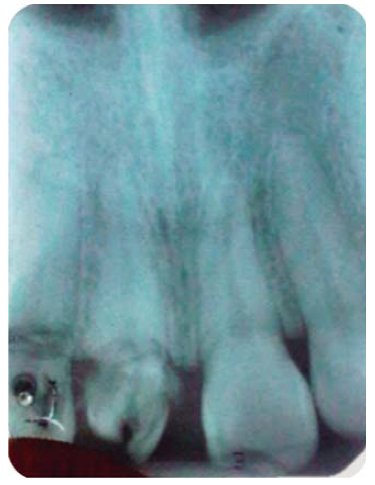

Paciente masculino de 21 años de edad, sano, presentando LDT al caer de una bicicleta; con fractura coronaria complicada de los dientes: 12, 11 y 21, con una evolución de 48 horas (Figura 1).

Debido a la evolución de dos días desde el accidente, el paciente presenta dolor e inflamación a la exploración extraoral, durante la exploración intraoral se observa la exposición pulpar de los dientes involucrados (Figura 2) e indica el tratamiento de urgencia a seguir, para disminuir el dolor e inflamación.